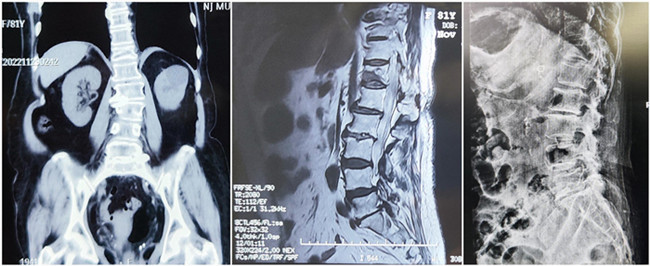

入院診斷:胸椎壓縮性骨折(T12)(主診斷);腰椎滑脫;腦梗死;高血壓1級;糖尿病。

*患者術(shù)前影像

王伯堯主任帶領(lǐng)其醫(yī)療團(tuán)隊(duì)通過與患者的詳細(xì)溝通與交流,綜合評估椎體成形術(shù)治療超高齡椎體壓縮性骨折患者的安全性更高,以及病患病情的復(fù)雜性,最終決定運(yùn)用智能化的手段,為患者制定個(gè)性化的手術(shù)方案,施行骨科機(jī)器人輔助下的T12經(jīng)皮椎體球囊擴(kuò)張成形術(shù)。